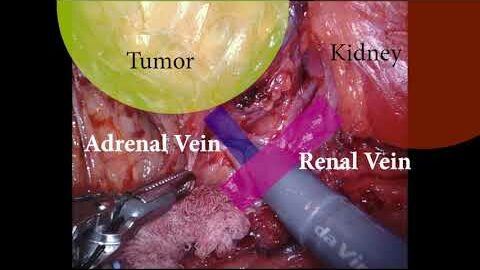

#365 R R C and Nephroureterectomy for Urothelial Carcinoma in a Double-Renal Transplant Recipient

KS Awards, Robotics, Surgeon ';